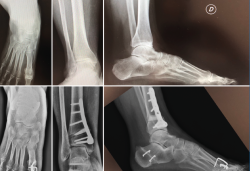

• Traumática: es la causa de hasta el 80% de las artrosis de tobillo en general y también la más frecuente de aquellas en valgo(1,2). En el caso de las artrosis asimétricas traumáticas en valgo la causa más frecuente son aquellas fracturas con compromiso articular con impactación del plafón tibial lateral (Figura 1A).

• Pie plano valgo del adulto (PPVA) (Figura 1B). La deformidad en PPVA es otra causa de artrosis asimétrica importante. No en vano la clasificación de Myerson y Bluman del PPVA tiene un grado específico para este escenario: el PPVA de grado IV(3).

Figura 1.